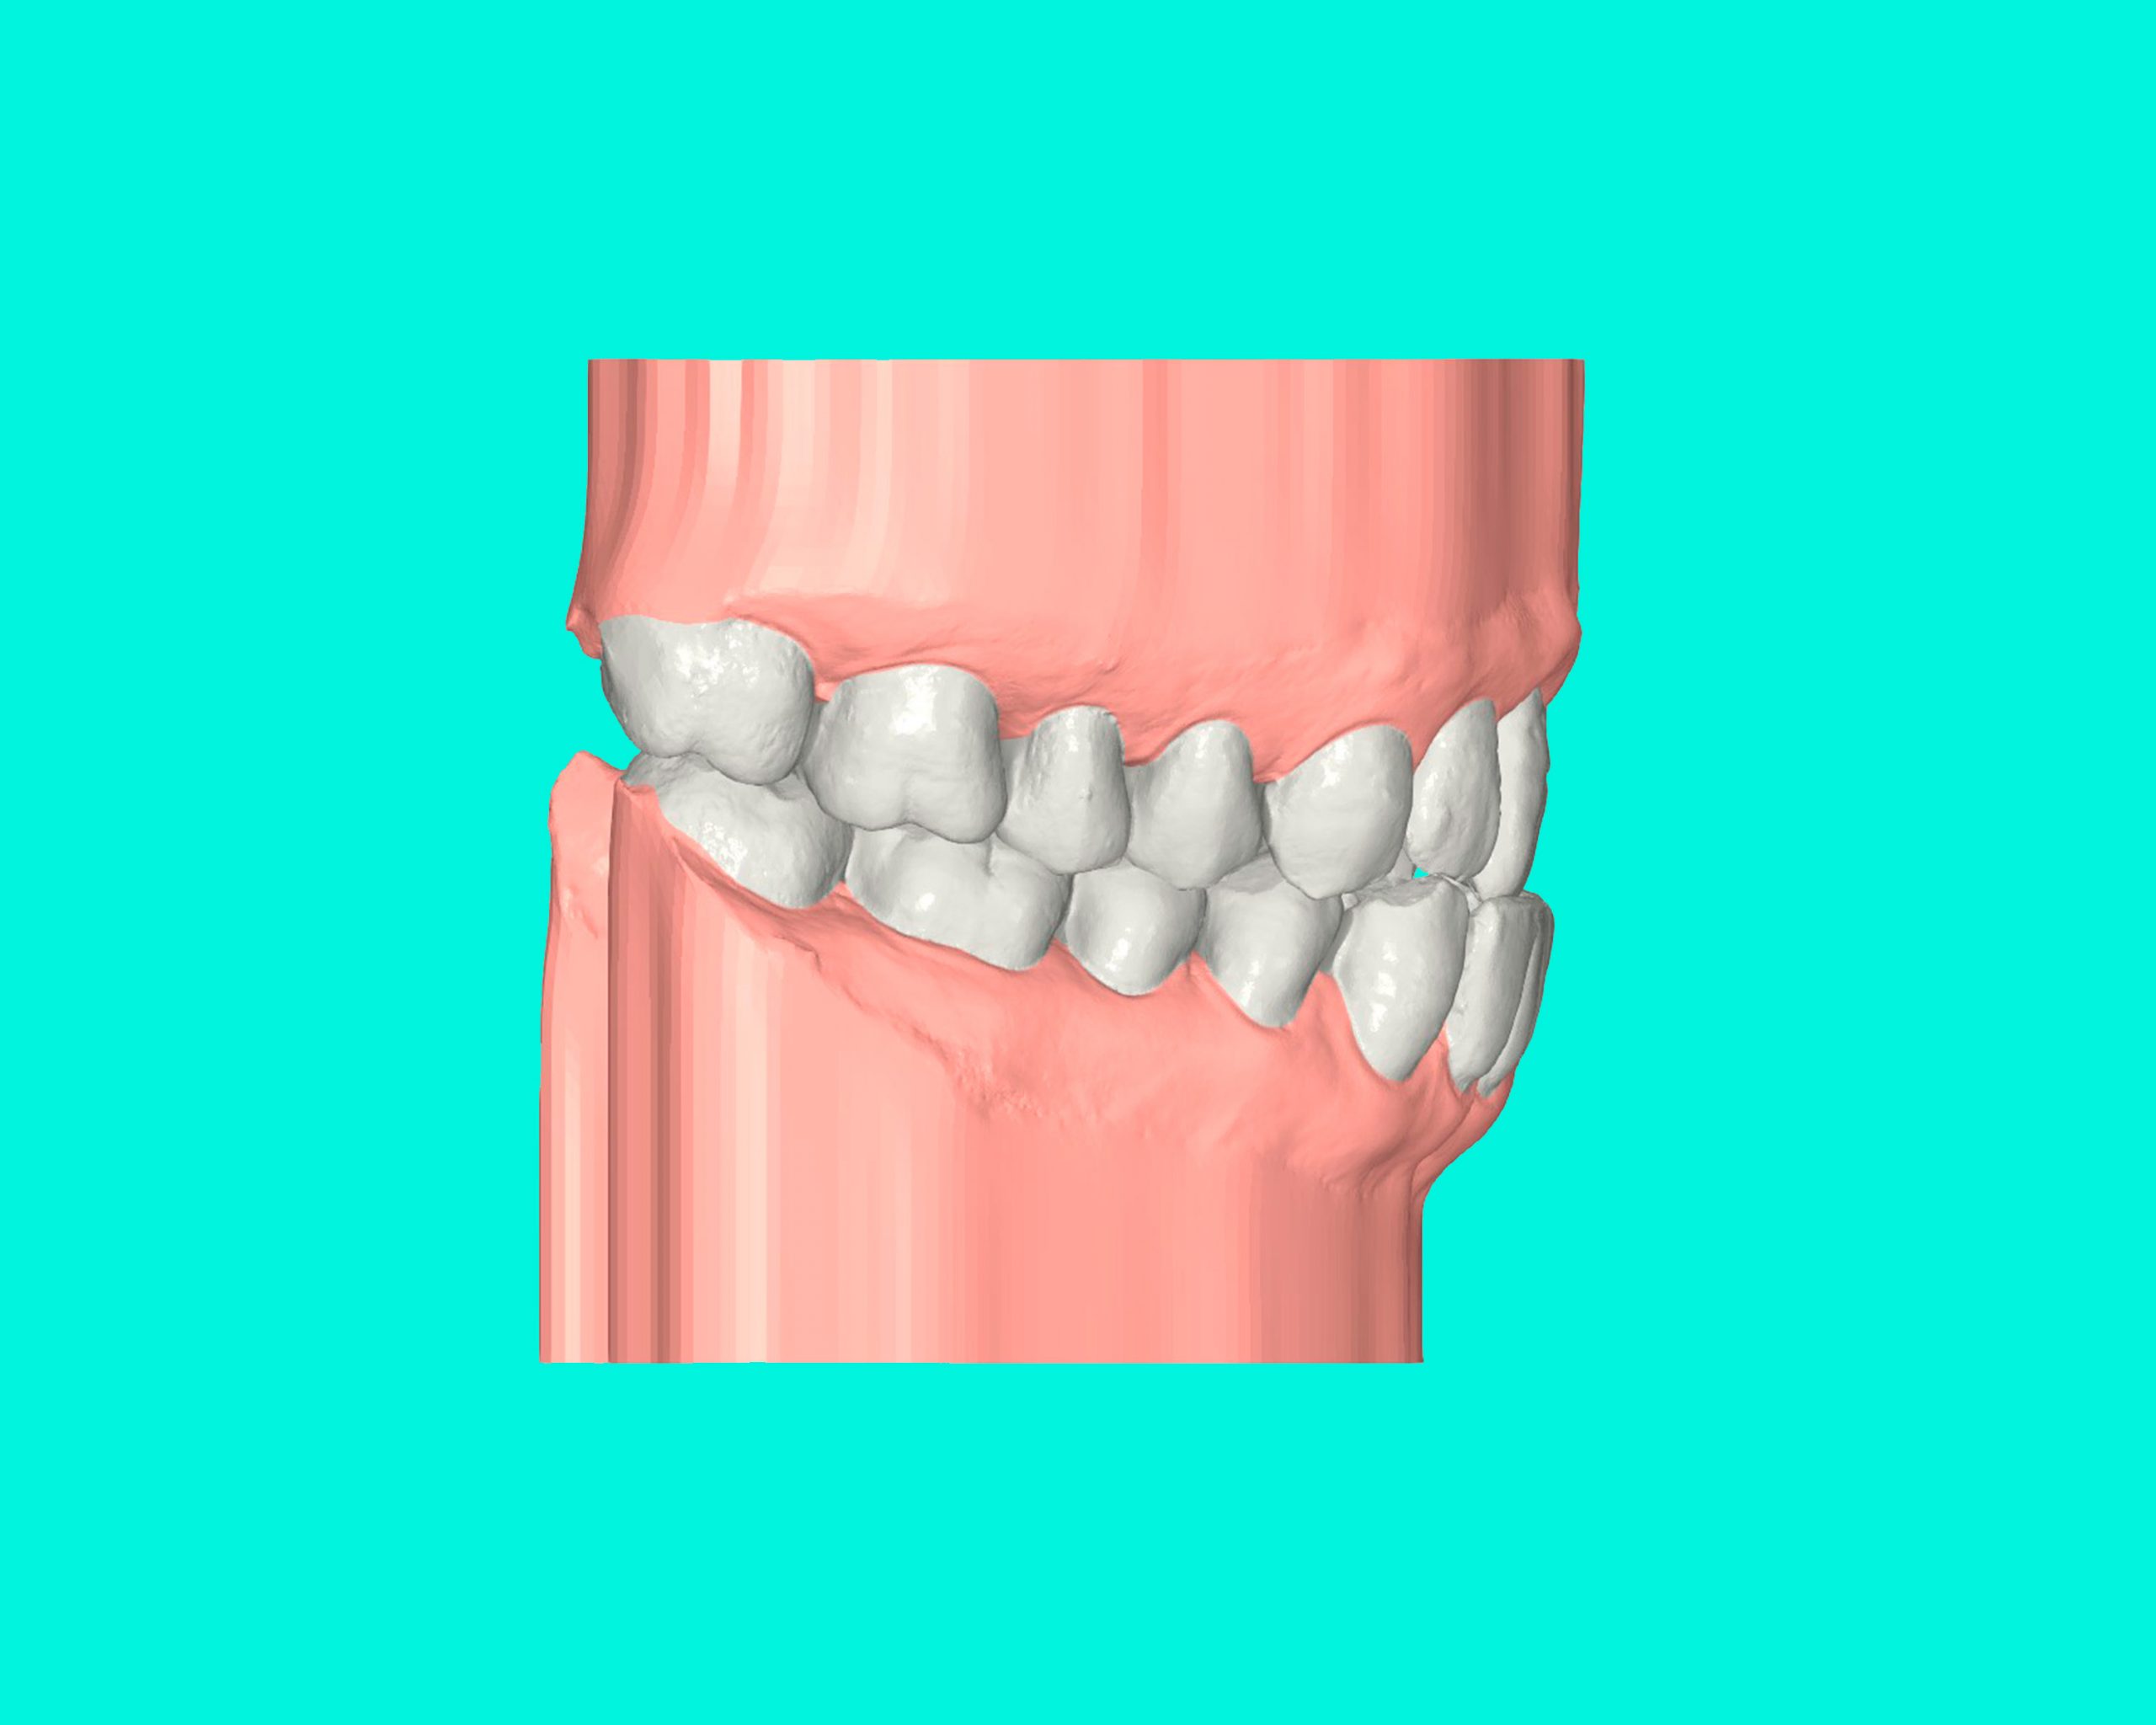

Maloclusión Clase III

La maloclusión dental de clase III se presenta cuando los dientes inferiores están más adelantados que los superiores, lo que provoca una sobremordida invertida.

Esta condición puede generar problemas en la mordida, dificultad para masticar y afectar la estética facial, especialmente en la proyección de la mandíbula.